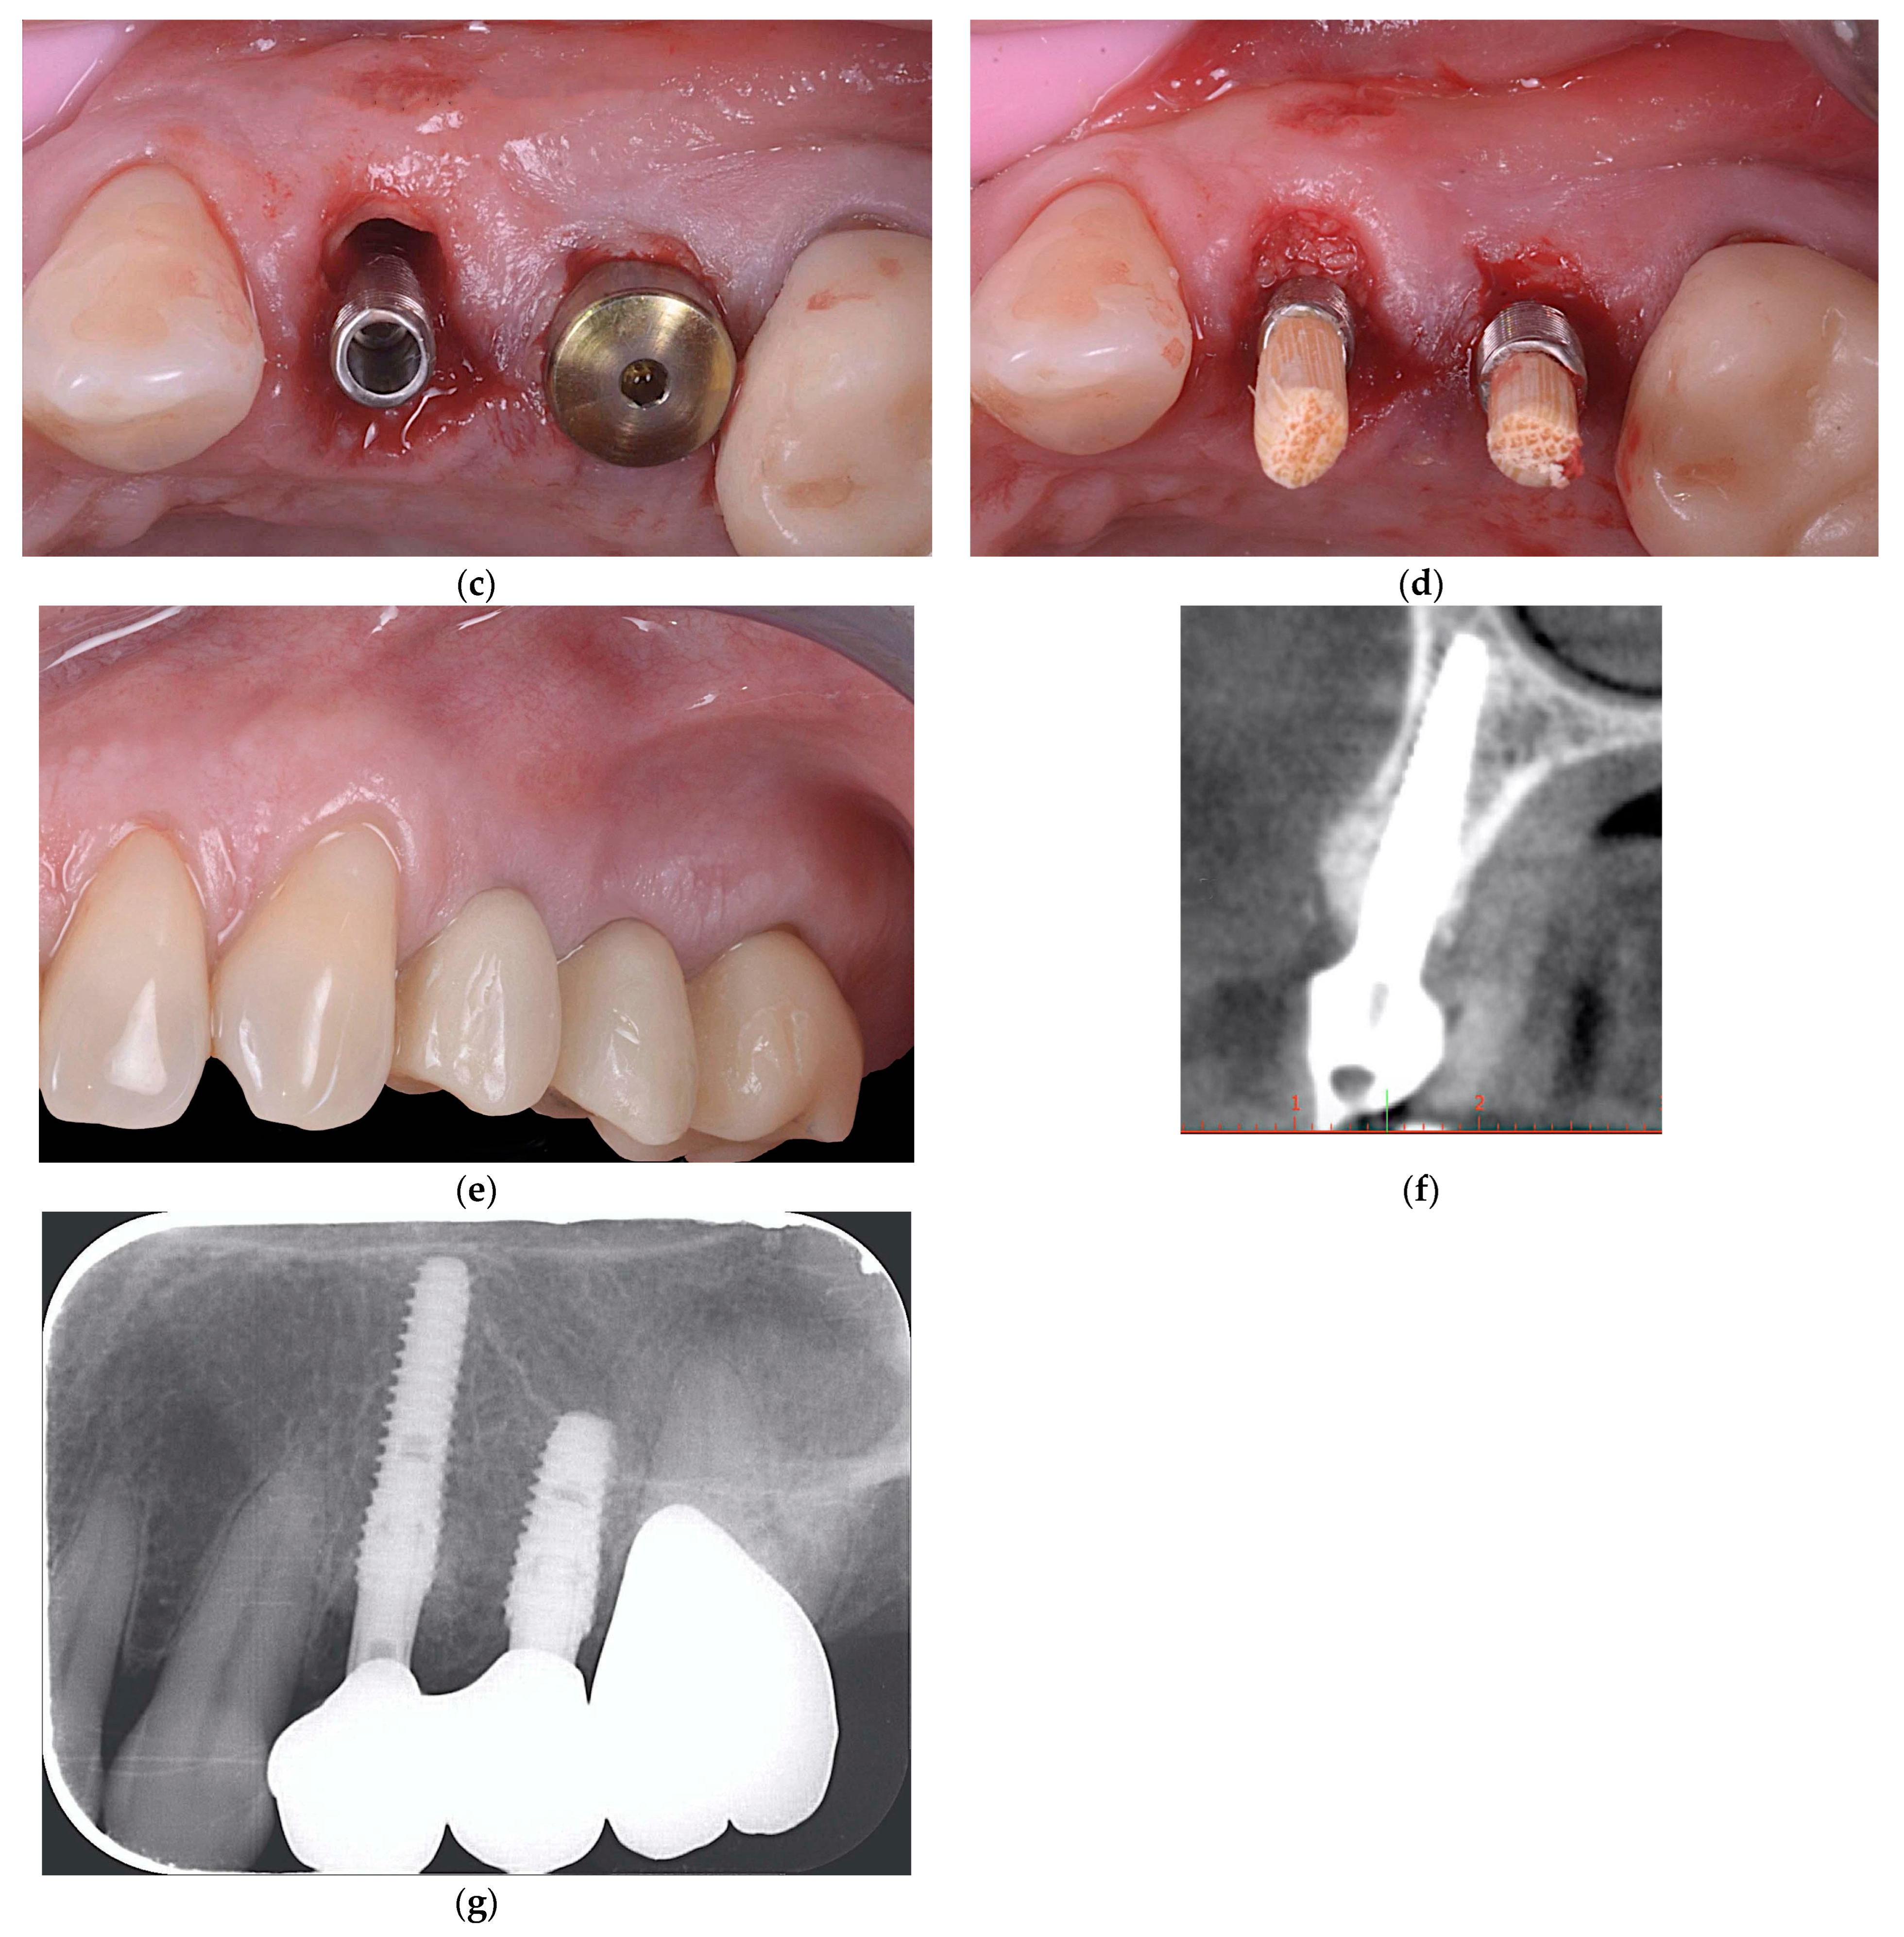

2.2.3. ARP and Delayed Implant Placement Using F.I.R.S.T.

2.3. Outcome Measures

- The success of the surgical interventions. The bone augmentation was deemed a successful one if a healthy soft and hard tissue situation could be achieved and implants were surrounded by at least 1.5 mm bone on the vestibular and oral sides.

- Horizontal bone gain (HBG) and vertical bone gain (VBG)

- Implant survival: